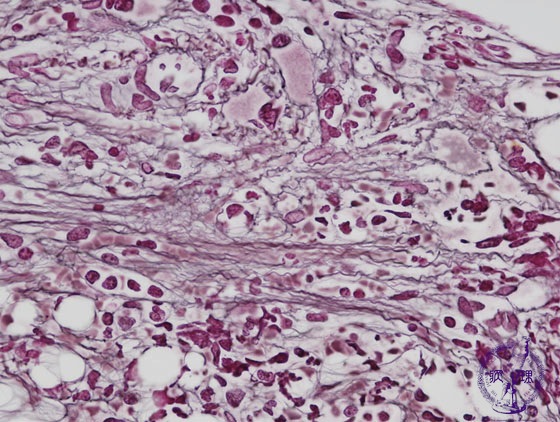

Microscopic image (reticulin stain, high power view): Black reticulin fibers are conspicuous in contrast with the normal marrow which rarely contains reticulin fibers.